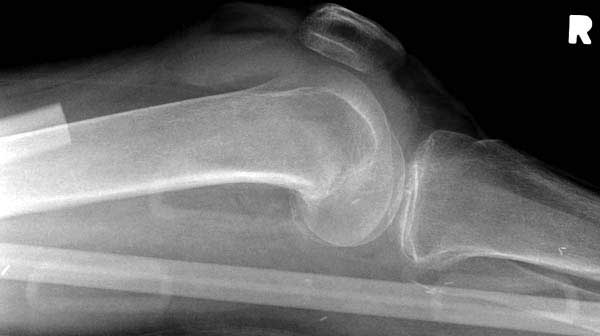

Обычно после чрезвертельных переломов, за исключением молодых, у пожилых остается нестабильность при движении. Часто падают и после 3х мес. в результате падения обнаружен перипротезный перелом (22-23), который зафиксирован Синтез пластиной.

Повторно поступает после двух с половиной лет, где обнаруживается перелом на второй стороне. Немного сложно, но для фиксации выбрали Antegrade InterTan Smith Nephew Nail и с момента фиксации более 3х мес.